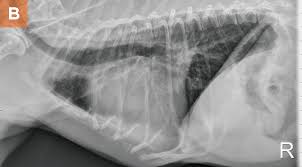

Lateral thoracic radiograph from a dog with a ventral alveolar pattern.

Lateral thoracic radiograph from a dog with a ventral alveolar pattern. That still leaves the question of why you should have recurrent pneumonia, unanswered and that is a question that will require further investigation. You can see on the left of the image a dark (relatively clear) lung. Pneumonia in people with lung cancer. The cause can be bacteria, a virus, or fungi. The problem here is that many things can enlarge the spleen above and beyond cancer. Note the increased soft tissue opacity in the lungs that partially obscures blood vessel margins. Various viruses, bacteria, and fungi can cause pneumonia. Differential diagnosis for common lung patterns in dogs and cats. I am a severe asthmatic and have had pneumonia on several occasions. This can happen when there is a high suspicion of cancer, for example, an enlarged spleen in a dog who is not acting right. Your veterinarian may recommend an fna and cytology or a biopsy, to confirm the diagnosis, and determine exactly what kind of lung cancer is present. Primary lung cancer are frequently located in the caudal (towards the hind end of the pet) lung lobes, however can be located in any lung lobe and are usually a single mass in the lungs, unless the tumor has spread.

Bacterial culture and drug sensitivity testing help the veterinarian to determine the best course of antibiotic treatment, if needed. His appetite is basically normal though his blood work shows that he is anemic. They did a cat scan and said the nod was.08 or 08 centimeters in dia. Note the increased soft tissue opacity in the lungs that partially obscures blood vessel margins. Bacterial pneumonia is an inflammation of the lung usually caused by bacterial or viral infection but can be caused by inhalation of an irritant. I am a severe asthmatic and have had pneumonia on several occasions. Your veterinarian may recommend an fna and cytology or a biopsy, to confirm the diagnosis, and determine exactly what kind of lung cancer is present. That still leaves the question of why you should have recurrent pneumonia, unanswered and that is a question that will require further investigation. The end stage of lung cancer in dogs is a very difficult time for dog owners as it's very hard to watch a beloved companion start giving up on life. Note the lobar sign with the caudal lung lobe. As these can also be caused by other disease, diagnostics include a full physical exam, blood work, radiographs, and may also require bronchoscopy with. A definitive diagnosis of lung cancer requires a sample of tissue (biopsy). This can happen when there is a high suspicion of cancer, for example, an enlarged spleen in a dog who is not acting right.